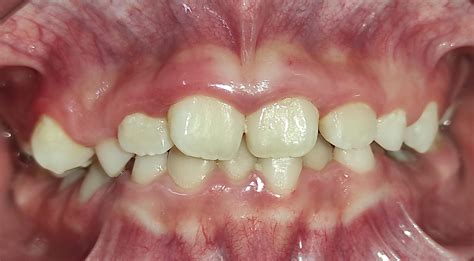

La característica común que define tanto un maxilar inferior prominente, como un maxilar superior retruído, es que en ambos casos el paciente presenta una maloclusión dental de Clase III, es decir, los dientes inferiores están delante de los dientes superiores, una condición que trasmite cierta dureza y agresividad a los rasgos faciales de los pacientes con este tipo de problema.